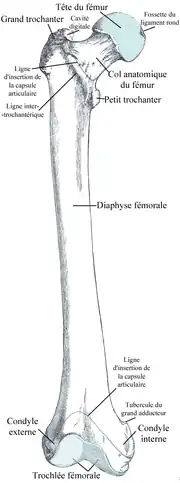

Extrémité supérieure du fémur

L'extrémité supérieure du fémur porte la tête fémorale qui s'articule avec l’acetabulum de l'os coxal constituant avec lui une articulation sphéroïde (ou énarthrose).

La tête fémorale est reliée au reste du fémur par le col fémoral. À l'union du col et de la diaphyse, se trouvent deux reliefs osseux, les petit et grand trochanters. Le petit trochanter se situant en dedans et en bas,et le grand trochanter en haut et en dehors. Ces deux saillies osseuses ou apophyses servent de sites d'insertions musculaires qui participent aux mouvements d'adduction, abduction, de flexion, d'extension et de rotaion de la cuisse sur le tronc.

Tête fémorale

La tête a la forme des 2/3 d'une sphère d'environ 24 mm de rayon, et est dirigée en haut (crânial), en dedans (médial) et un peu en avant (ventral). Sa surface convexe, dirigée en haut et en avant, est lisse, enrobée de cartilage hyalin, à l'exception d'une dépression ovoïde ; la fossette de la tête (fovea capitis femoris), située un peu en dessous et en arrière de son centre, constitue la zone d'insertion du ligament de la tête du fémur (ligamentum capitis femoris), ou ligament rond.

Col fémoral

Le col est un processus osseux plus ou moins cylindrique, reliant la tête fémorale au massif osseux constitué des petit et grand trochanter. Il forme avec l'axe principal du fémur un grand angle : l'angle cervicodiaphysaire fémoral ouvert en dedans. Il mesure chez l'adulte de 130° à 135°, une variation entre 120 et 140° est considérée comme normale.Il mesure 150° chez le nouveau-né et diminue durant la croissance.

En plus de se projeter supérieurement et médialement par rapport à la diaphyse, le col présente également un angle d'antéversion (portant la tête fémorale en avant) variable selon les individus, allant en général de 10° à 15°.

Si l'angle cervicodiaphysaire est supérieur à 130° on parle de coxa valga, et s'il est inférieur à 110° on parle de coxa vara. Plus l'angle est petit, plus il y a un risque de fracture du col du fémur (ce qui permet d'expliquer, en lien avec l'ostéoporose, la fréquence plus élevée de ce type de fracture chez le vieillard).

Trochanters

Les trochanters sont les proéminences osseuses situées à la base du col fémoral.

Les deux trochanters sont reliés à l'avant par la ligne inter-trochantérique et à l'arrière par la crête inter-trochantérique.

Grand trochanter

Le grand trochanter (trochanter major) est une éminence quadrilatérale située à la jonction du col fémoral avec la partie supérieure du corps. Il est situé légèrement latéralement et postérieurement au grand axe du fémur. Chez l'adulte, il est environ 1 cm plus bas que la tête fémorale. Il a deux faces et quatre arêtes. La surface latérale sert d'insertion au muscle moyen glutéal (gluteus medius, ancien muscle fessier moyen). La surface médiale, plus petite que la latérale, présente à sa base une dépression, la fosse trochantérienne (fossa trochanterica, ancienne fossette digitale), où s'insère le tendon du muscle obturateur externe (obturator externus). Au-dessus et en avant se trouvent le lieu d'insertion du muscle obturateur interne et des muscles jumeaux supérieur et inférieur. L'arête supérieure est le lieu d'insertion du muscle piriforme. L'arête inférieure donne naissance à la partie supérieure du muscle vaste latéral (vastus lateralis). L'arête antérieure est proéminente, le muscle petit glutéal (gluteus minimus, ancien petit fessier) s'y rattachant.

Petit trochanter

Le petit trochanter (trochanter minor) est une éminence conique variable en grosseur. Il se projette de la partie inféro-postérieure de la base du col. À son sommet s'attache le tendon du muscle ilio-psoas.

Corps du fémur

En coupe horizontale, la diaphyse fémorale montre un corps triangulaire à sommet postérieur.

Il présente trois faces : antérieure, latérale et médiale, séparées par trois bords : postérieur, antéro-médial et antéro-latéral. Ces deux derniers sont émoussés tandis que le bord postérieur est bien marqué par la ligne âpre.

Ligne âpre

La ligne âpre est une crête osseuse s'étendant verticalement sur la hauteur du fémur, se trifurquant en haut et se bifurquant en bas. Elle se trouve entre les faces postérieure et postéro-externe du corps du fémur formant son bord postérieur. Elle se compose de deux lèvres qui s'évasent en haut et en bas mais se rejoignent sur toute la partie moyenne de l'os. On décrit une lèvre médiane et une latérale. Sur la lèvre médiane s'insère le muscle vaste médian du quadriceps, alors que sur la lèvre latérale s'insèrent le muscle vaste latéral du quadriceps, le muscle grand fessier et le muscle biceps fémoral par son ventre court. Entre les deux lèvres s'insèrent les différents muscles adducteurs de la cuisse. À cela s'ajoute la branche moyenne, de trifurquation, sur laquelle s'insère le muscle pectiné.

Extrémité inférieure du fémur

L’extrémité inférieure du fémur est volumineuse et de forme cuboïde. Sa largeur est plus grande (60 à 65 mm) que son épaisseur antéro-postérieure (50 à 53 mm). A ce niveau le fémur se recourbe légèrement d'avant en arrière.

Elle porte à l'avant la surface patellaire du fémur qui forme une surface articulaire de type trochlée et qui répond à la surface articulaire de la patella.

Cette surface se poursuit en arrière par deux surfaces articulaires séparées par la fosse intercondylaire et formant les condyles médial et latéral du fémur qui répondent aux condyles médial et latéral du tibia.

Les deux condyles sont surmontées par deux tubercules osseux : les épicondyles latéral et médial du fémur.

L'ensemble de ces surfaces articulaires contribue à l'articulation du genou.